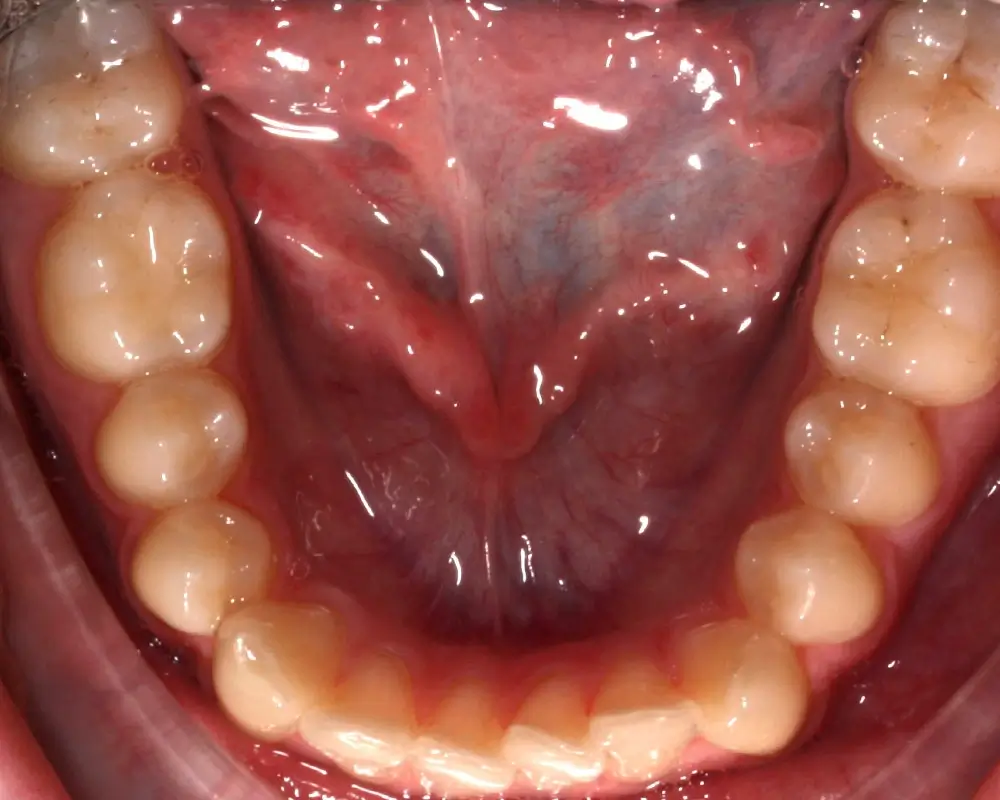

Скученность - Кейс 25

Эффективность устранения дефекта прикуса посредством элайнеров FlexiLigner.

16

Количество кап НЧ

Результаты лечения